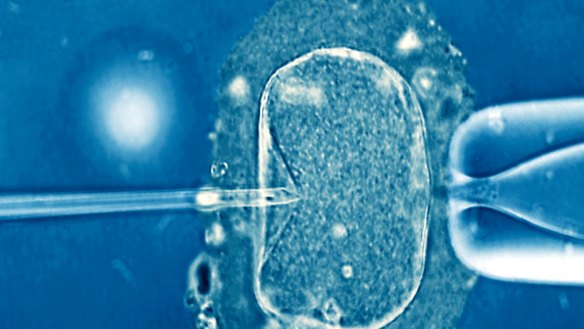

More women are seeking the services of fertility clinics.